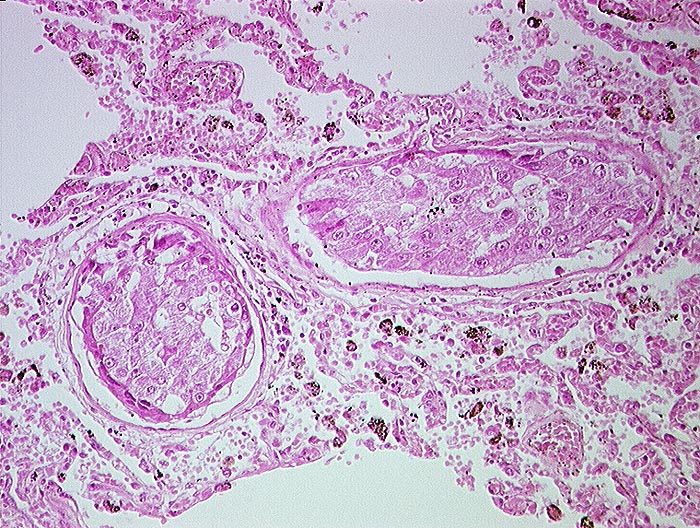

Hepatozelluläres Karzinom : Tumorembolien

Lunge

Solide Tumorzellaggregate in Pulmonalarterienästen. Die Tumorzellen haben grosse Ähnlichkeit mit Leberzellen.

Hepatozelluläre Karzinome haben die Tendenz sich in Form von Tumorembolien in die Lungen auszubreiten.